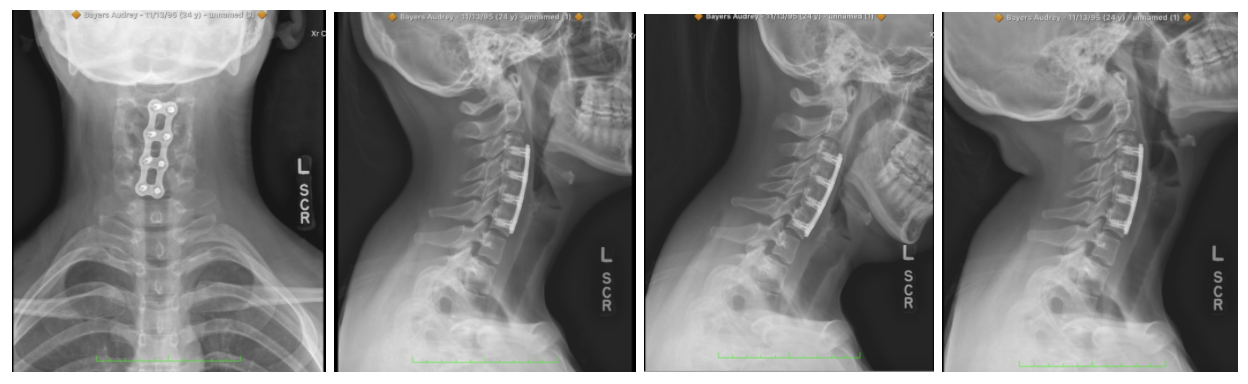

Audrey sustained injuries in her neck at three levels, C3-C4, C4-C5, and C5-C6. Before her initial surgery, she underwent many physical therapies, countless trigger point injections, and took various pain medications. Ultimately, a board-certified neurosurgeon performed a 3-level Anterior Cervical Decompression Fusion, with iliac crest bone bank fusion, and micro section cervical planting at C3 to C6. Audrey was planted with three 8mm spacers tricort dual convex; level III reflects hybrid plates 45mm, and fixed angle self-drilling screws.